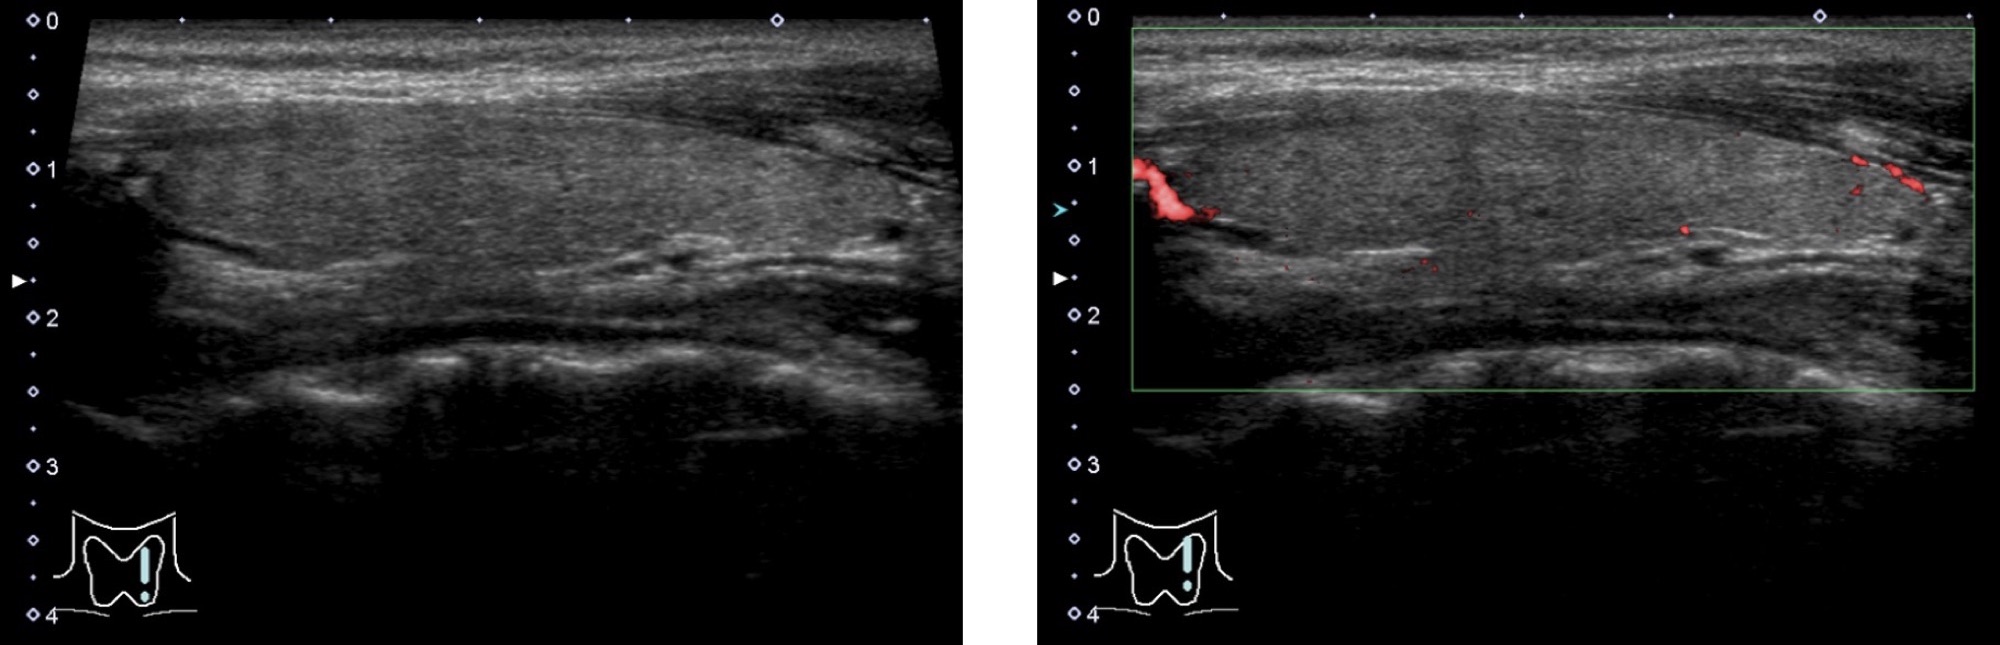

正常甲状腺 の超音波画像

正常な甲状腺は、周りの筋肉よりも白く (エコーレベルが高く) 見えます。